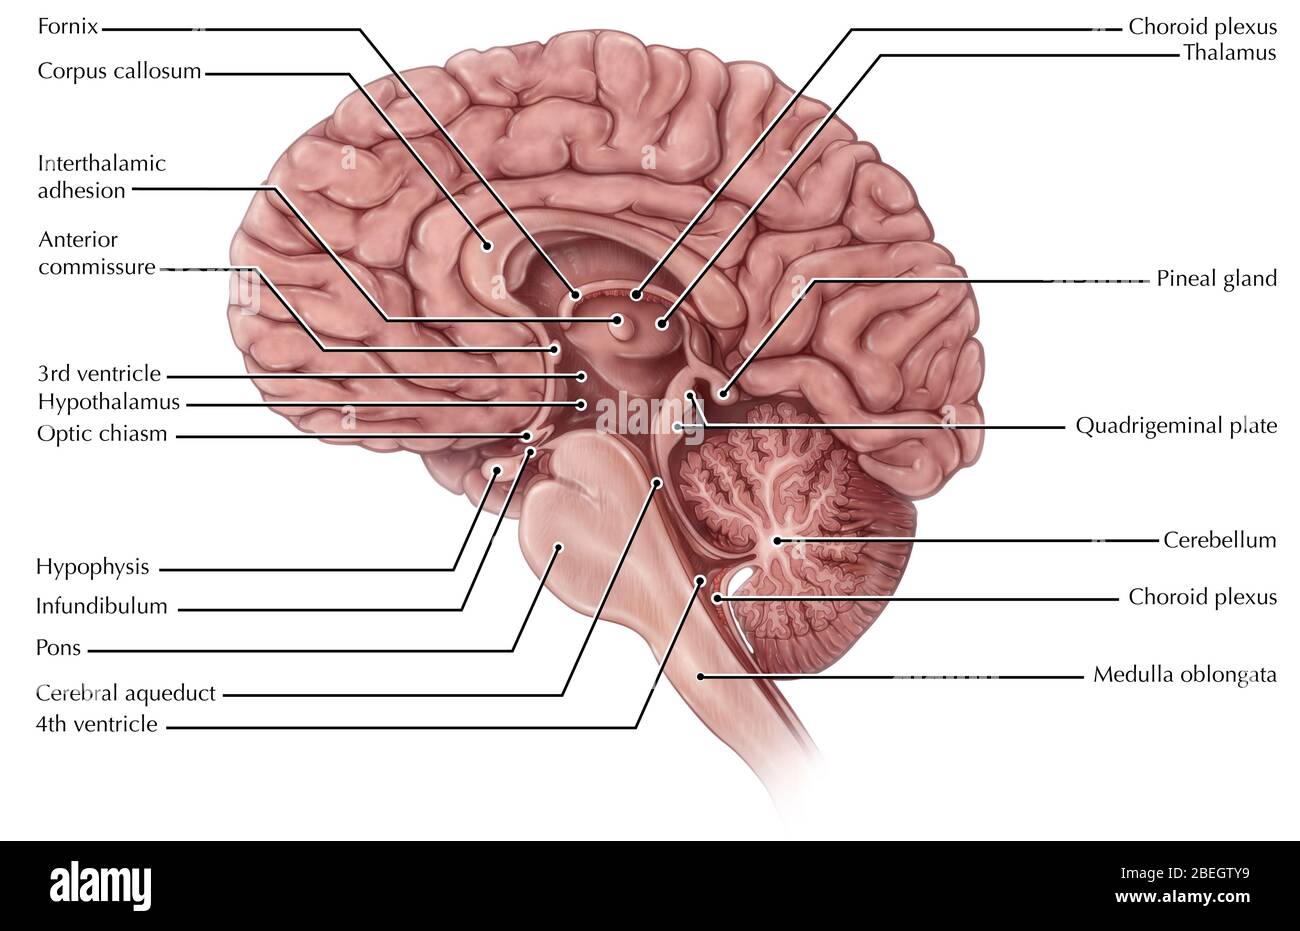

RMBCE641–Sagittale Abschnitt des menschlichen Gehirns, Darstellung von Strukturen der zerebralen Ventrikel, Kleinhirn und Hirnstamm.

RMPFYB74–. Cunninghams Lehrbuch der Anatomie. Anatomie. PAETS abgeleitet aus dem ZWISCHENHIRN. 617 davon, welche das Aquädukt umgibt, ist direkt kontinuierlich mit der grauen Substanz der substantia perforata posterior und Tuber cinereum, und auf diese Weise kommt es zu der Oberfläche in der Unterseite des Gehirns. Die optic Chiasma kreuzen den Boden vor und markiert die Stelle, wo der Letzteren stetig mit der anterioren Wand des Hohlraums wird. Die vordere Wand des dritten Ventrikels wird durch die Lamina terruinalis, die sich nach oben erstreckt sich von der Optic chiasma gebildet. Die anteriore com-missure, wie es kreuzt von einem

RM2AWFNN9–Menschliche Anatomie, einschließlich Struktur und Entwicklung und praktische Überlegungen d in einem sagittalen mesialen Abschnitt (Abb. 910) wird jede dieser Teilungen als mit einem Teil des Systems der Kommunikation von Räumen verwandt angesehen, die als die dritten Ventrikel des Lateralands, der Aquädukt von Sylvius und der vierte Ventrikel die oben genannten Gehirnhemisphären ausdehnen. Durch den Hirnstamm und unter dem Kleinhirn bis zum zentralen Kanal des Rückenmarks. Da die lateralen Ventrikel zwei innumerieren, ist die Theirstellung im Zusammenhang mit den Gehirnhemisphären, in denen sie liegen, lateral zum m

RM2AN4TWY–Handbuch der allgemeinen, beschreibenden und pathologische Anatomie (Band 2). Ventrikel, ein. Ventrikel des Kleinhirns, b. Aquädukt von Sylvius, C. Dritten Ventrikel, d. Lateralen Ventrikel, 1. Vordere Horn, 2. Hintere Horn, 3. Absteigend Horn, II. Textur, III. Gewicht, IV. Konsistenz, Kap. Iii. Umhüllt des Gehirns. Abt. Ich. Pia - mater, I. des Rückenmarks, II. Von Hirn, ein. - Externe Pia mater, b. Interne pia-mater, ich. Choroid Plexus des vierten Ventrikel, ii. Choroid Plexus des Großhirns, Art.ii.Apert-syndrom Membran, Art. hi. Dura-mater, I. spinalen Dura-mater, II. Zerebrale Dura-mater